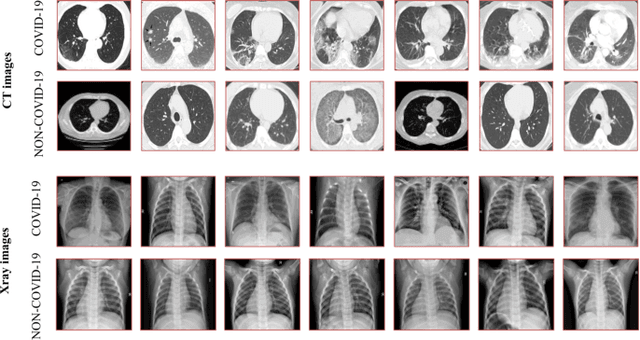

Abstract:This paper proposes to encode the distribution of features learned from a convolutional neural network using a Gaussian Mixture Model. These parametric features, called GMM-CNN, are derived from chest computed tomography and X-ray scans of patients with Coronavirus Disease 2019. We use the proposed GMM-CNN features as input to a robust classifier based on random forests to differentiate between COVID-19 and other pneumonia cases. Our experiments assess the advantage of GMM-CNN features compared to standard CNN classification on test images. Using a random forest classifier (80\% samples for training; 20\% samples for testing), GMM-CNN features encoded with two mixture components provided a significantly better performance than standard CNN classification (p\,$<$\,0.05). Specifically, our method achieved an accuracy in the range of 96.00\,--\,96.70\% and an area under the ROC curve in the range of 99.29\,--\,99.45\%, with the best performance obtained by combining GMM-CNN features from both computed tomography and X-ray images. Our results suggest that the proposed GMM-CNN features could improve the prediction of COVID-19 in chest computed tomography and X-ray scans.